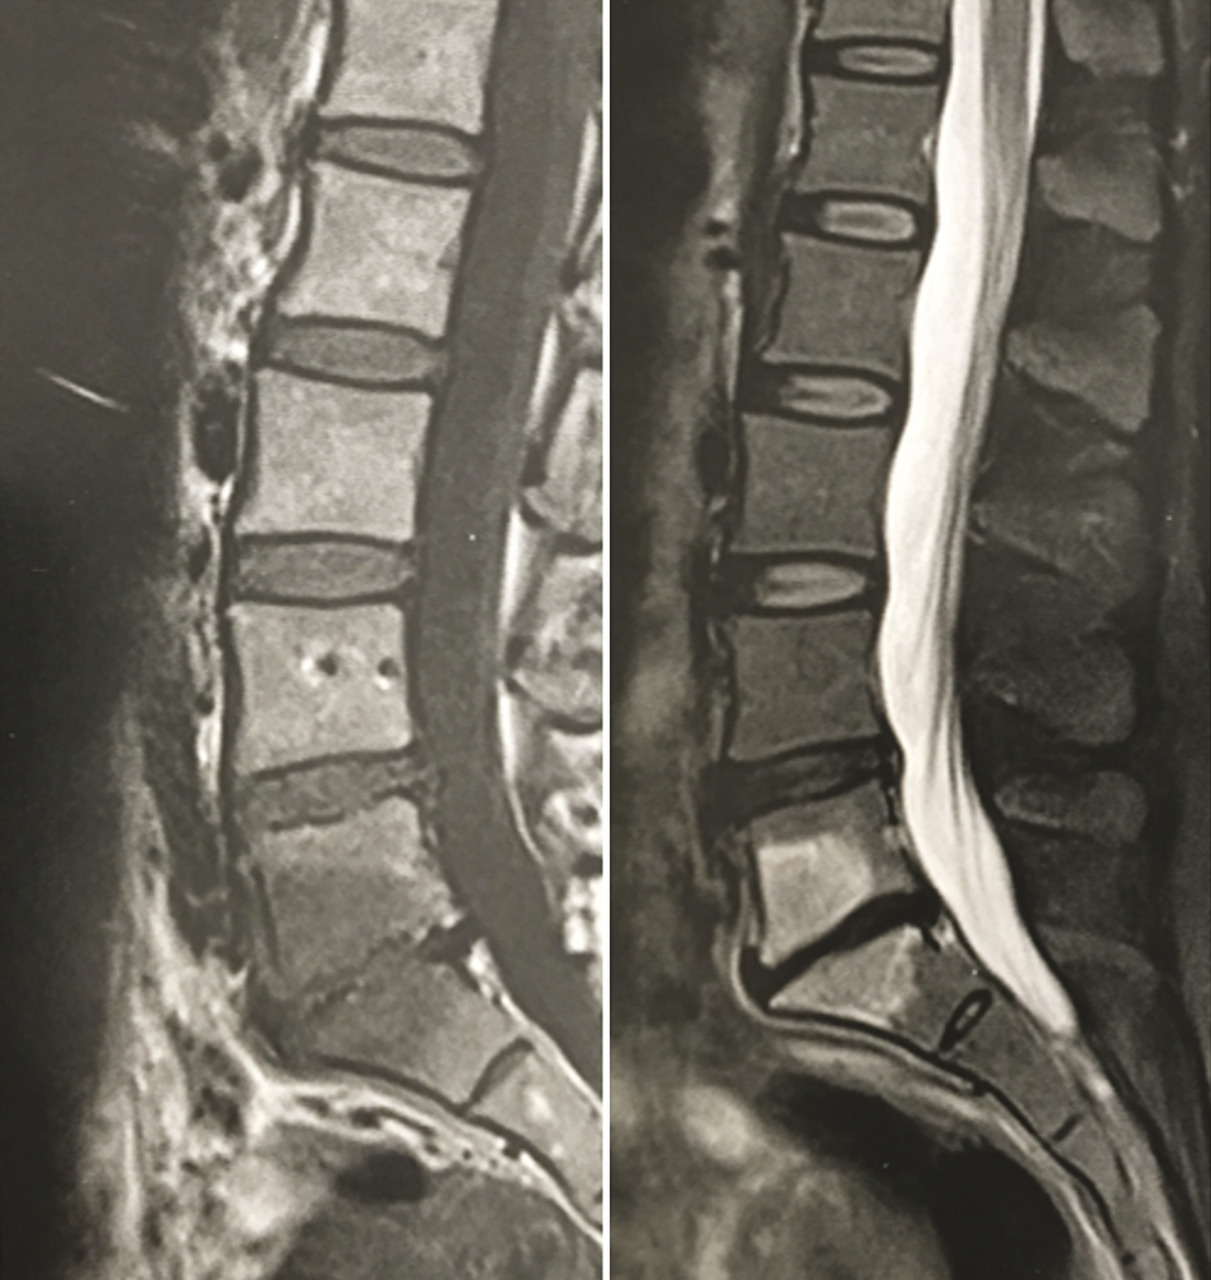

Pour atteindre l’espace épidural, on peut utiliser les voies interépineuse, interlamaire (fig. 1 et 2) ou transforaminale.3, 4 Il existe en outre, à l’étage lombaire, une voie caudale par le ­hiatus sacro-coccygien, mais qui ­nécessite d’injecter au moins 20 mL pour atteindre les racines L4 et L5.5 Tous ces abords se font sous guidage fluoroscopique ou tomodensitométrique, avec injection préalable de produit de contraste, pour vérifier la bonne position de l’aiguille.

Spécificités du kyste synovial articulaire postérieur

Un kyste synovial développé aux ­dépens d’une articulation interapophysaire postérieure peut provenir de l’arrière et comprimer l’émergence d’une racine nerveuse (fig. 3). Il constitue une cause relativement fréquente de lomboradiculalgie du sujet d’âge mur. Ce kyste se développe à partir d’une arthropathie postérieure dégénérative, habituellement érosive, et est associé dans deux tiers des cas à un spondylolisthésis dégénératif.9 Une injection de corticoïdes dans l’articulation postérieure à l’origine du kyste permet de faire céder durablement la radiculalgie dans un tiers des cas. En revanche, si la radiculalgie persiste ou récidive sous bref délai (< 6 mois), de nouvelles injections sont, en règle générale, inefficaces. Il faut donc recourir à l’exérèse chirurgicale du kyste, parfois associée à une stabilisation, s’il existe des signes d’instabilité vertébrale.9

La plupart des rhumatologues français réalisent les injections de corticostéroïdes dans les articulations interapophysaires postérieures pour passer un cap douloureux aigu, dans les cas où l’examen clinique ou la ­présence d’un hypersignal « œdémateux » en IRM, sur les séquences ­pondérées en T2 avec suppression du signal de la graisse (fig. 4), suggè­rent qu’elles peuvent être en partie responsables des douleurs. Cependant, des essais randomisés n’ont pas pu mettre en évidence de supériorité des injections de corticoïdes dans les articulations postérieures, par rapport à des injections intra-arti­culaires de sérum salé.10, 11 Par ailleurs, il n’y a pas de place, d’une façon générale, pour un geste percutané intradiscal dans les lombalgies chroniques communes, car leur cause est multifactorielle et toujours incertaine.

Le cas des discopathies dégénératives dites « actives », avec un signal « œdémateux » (hypersignal T2) des plateaux vertébraux en IRM (« Modic 1 ») est particulier (fig. 4). C’est le seul signe radiologique qui soit bien corrélé aux lombalgies. D’où la tentation de traiter les patients par des injections locales de corticoïdes.12 Un essai randomisé chez des lombalgiques exprimant un signe de « Modic 1 » a montré que l’efficacité d’une injection intradiscale de corticoïdes, sur la lombalgie, est supérieure à celle d’une injection intradiscale de sérum salé à un mois (-2,4/10 points sur une échelle visuelle analogique douleur), mais pas à trois mois ou ultérieurement.13 Ce bénéfice paraît trop éphémère pour justifier l’usage de cette voie d’administration, qui comporte un risque, faible mais ­certain, de spondylodiscite infectieuse iatrogène. Dans cette situation, il paraît plus raisonnable de se limiter à des injections épidurales locales de corticoïdes ou à une faible corti­co­thérapie per os.